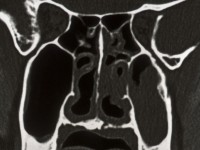

| lymfoom

in bijholten |

X-sinus, of nog beter direct een CT-scan of MRI van de schedel. Verder bloedonderzoek